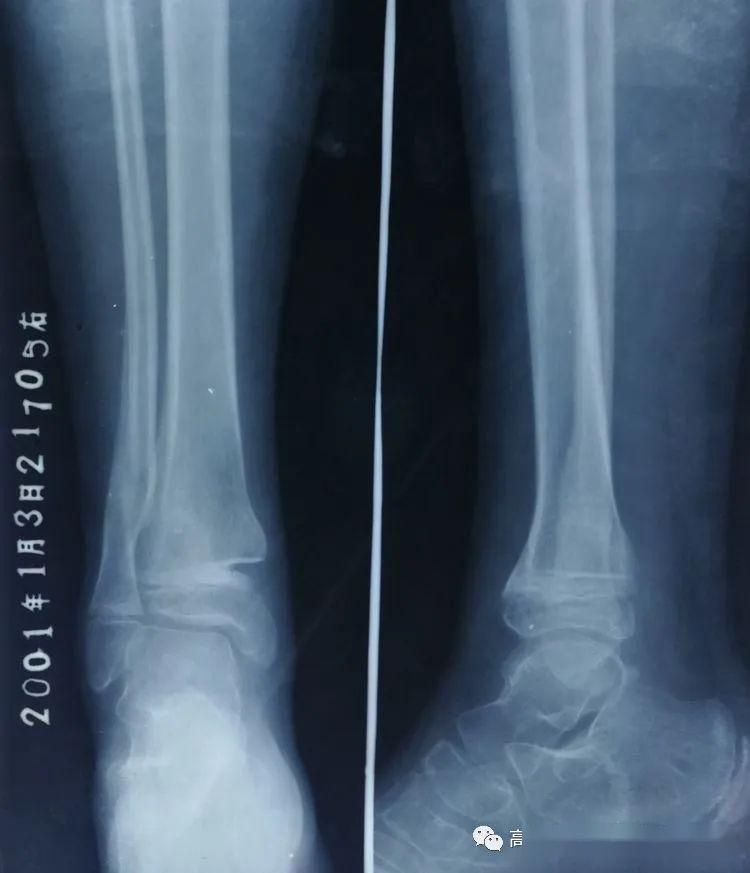

外踝可见斜形骨折线,可见折线穿破踝关节面,骨折断端未见错位分离影像